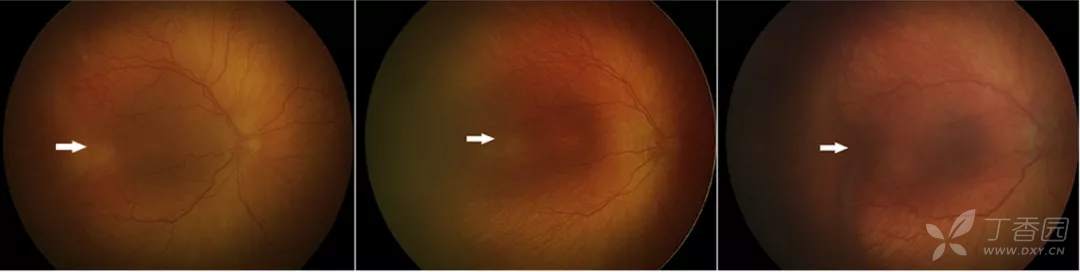

图. 激光治疗后的消退。左图为3期ROP伴plus病变治疗前;中图为治疗1周后3期病变变薄、变白。右图治疗后1个月病变消退。